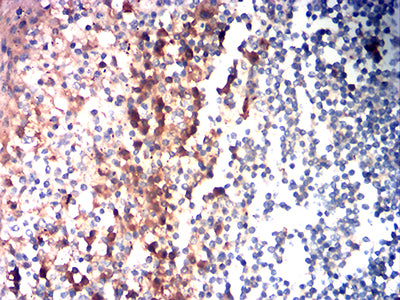

Immunohistochemical analysis of paraffin-embedded human tonsil tissues using CD85G mouse mAb with DAB staining.